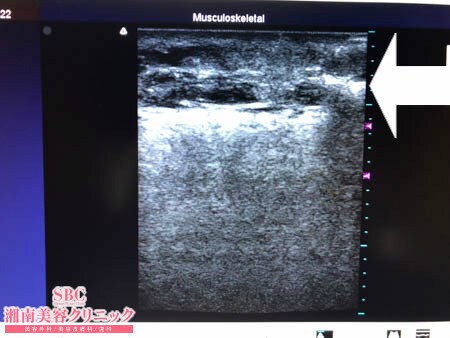

No.206799【脂肪吸引】【動画あり】湘南美容外科全ドクターの脂肪吸引最高責任者である竹田先生による脂肪吸引のフォトギャラリー!スタッフさんからの脂肪吸引のご依頼は何よりも信頼の証!上背部術中3Dタッチビュー・右ブラジャー下

背中はそもそも皮膚が分厚く硬く

その下に潜んでいる皮下脂肪自体も

非常に硬く線維質で脂肪吸引しにくいもの。